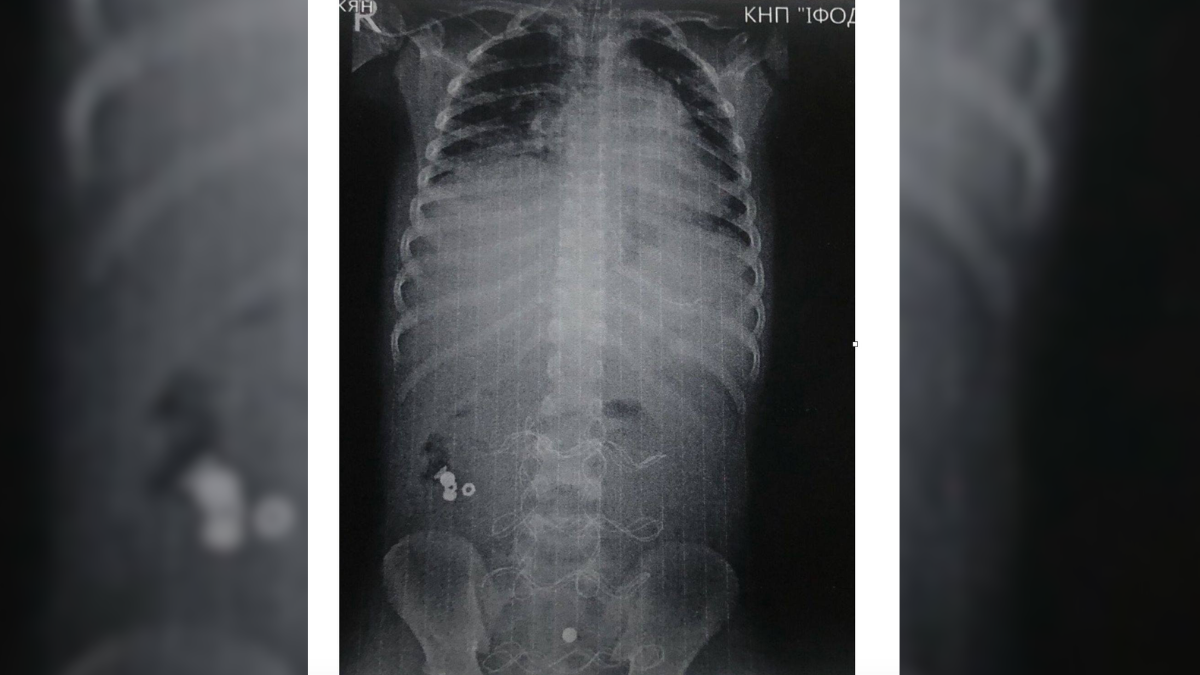

Дитину привезли до лікарні у вкрай тяжкому стані інфекційно-токсичного шоку з клінікою розлитого перитоніту. З’ясувалось, хлопчик проковтнув батарейку, що спричинило перфорацію тонкого кишківника.

Передопераційна підготовка тривала 12 годин. Загалом було проведено 3 оперативних втручання. 20 діб знадобилось, щоб дитину можна було виписати з лікарні у задовільному стані.